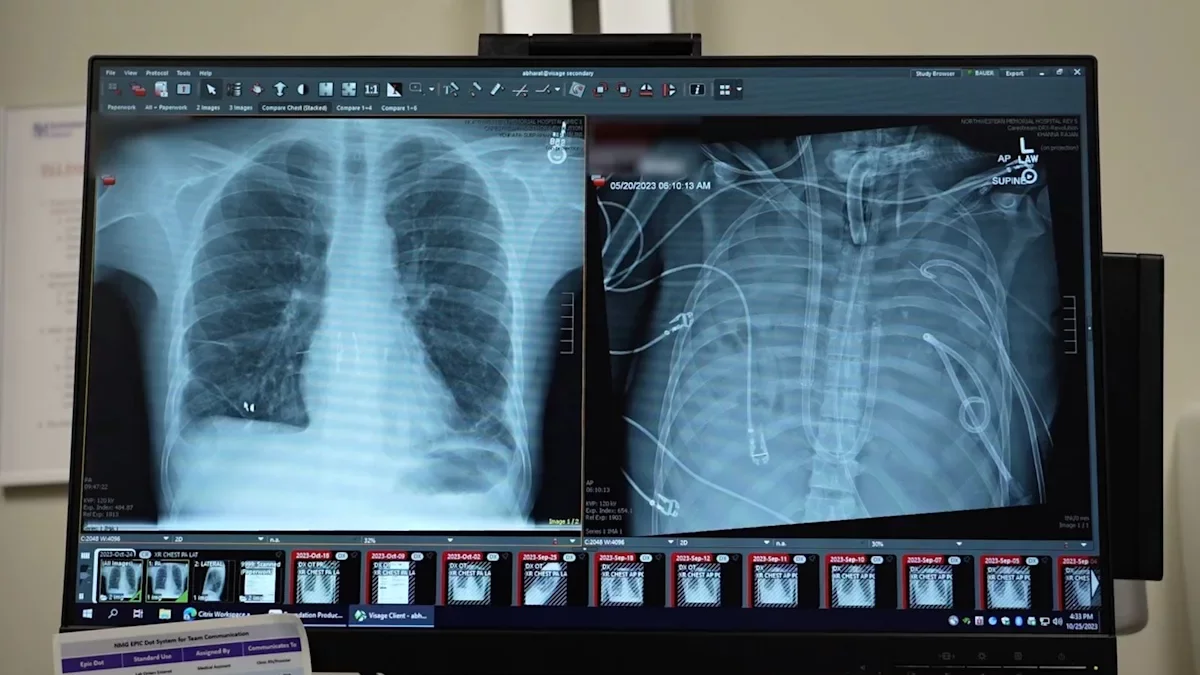

Un equipo de científicos ha conseguido que un paciente con una grave afección pulmonar sobreviva gracias a un sistema pulmonar extracorpóreo que le mantuvo vivo hasta que se le pudo realizar un doble trasplante de pulmón, una estrategia que podría emplearse como «puente salvavidas» hasta la intervención, según un estudio.